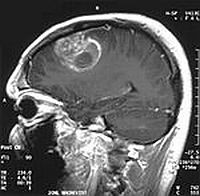

Koleszterinnel táplálkozó agydaganat... Ahogy bizonyos daganatfajták – például néhány mellrák-típus és a prosztatarák – hormonfüggő, úgy egy gyakori agydaganat kialakulásában az LDL-koleszterin játszik fontos szerepet.

Amerikai tudósok felfedezése, hogy a legtöbb glioblasztóma koleszterinfüggő, szerintük új gyógyszerek kifejlesztésére ad lehetőséget. A glioblasztómák 90 százaléka rendelkezik a "hiperaktív jelzőúttal" a koleszterinre. Ez azt jelenti, hogy a sejtjeik programozása miatt magukba szippantják az LDL-koleszterint, mely miatt tovább növekednek.

glioblastoma-d0000118B2f96ac84c8e1

Az eredmények emberi agydaganatsejtek laboratóriumi vizsgálataiból és állatkísérletekből származtak. Nagy-Britanniában évente kb. 5 000 új agydaganatos esetet diagnosztizálnak, 3 600 beteg hal bele. A glioblasztóma multiforme felnőtteknél fordul elő leggyakrabban. A legagresszívabb daganattípusok egyike, kezelése igen bonyolult. A felfedezésétől számítva átlagosan 15 hónap túlélési időre lehet számítani.